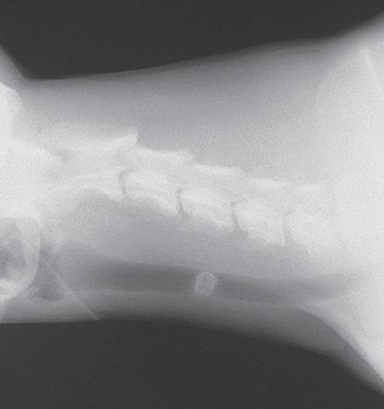

| 5m, English bulldog, respiratory distress | 8y, Yorkshire Terrier, respiratory distress | |

![]() | ![]() | |

| ์์ธ | 5๊ฐ์๋ น + ์๊ธ๋ฆฌ์ ๋ถ๋ | ์ ์ฒ์ ์ผ๋ก risk factor๋ฅผ ๊ฐ์ง๋ง, ๋ฐ์์ middle-aged์์ + ์ํ๊ฒฌ ๋ค๋ฐ |

| ๊ธฐ๊ด ์ง๊ฒฝ | ์ ์ฒ์ ์ผ๋ก dorsal band ์์ด ํ์ด๋จ โ ๊ฒฝ๋ถ๋ถํฐ trachea๊น์ง ์ผ๊ด์ ์ผ๋ก diameter๊ฐ ์ข์. | ์ง๊ฒฝ ๊ฐ์๊ฐ ์ผ๊ด์ ์ด์ง ์๋ค. ์ ์์ธ ๊ณณ๋, ์ข์์ง ๊ณณ๋ ์์. |

| ์ด์ง | ๋ง์ ธ๋ณด๋ฉด ๋ฑ๋ฑํจ. | ๋ง์ ธ๋ณด๋ฉด ์ฐ๊ธ์ฐ๊ธํจ. |

| ์ง๋จ | Tracheal hypoplasia | Tracheal collapse |